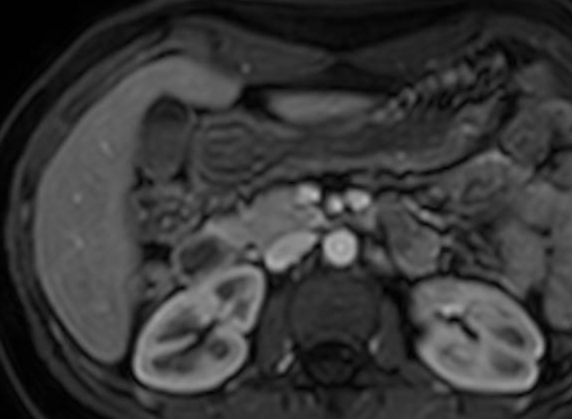

Figure 1 Radiologische Diagnostik Der Gallenblase Und Der Gallenwege Teil 2 Springerlink